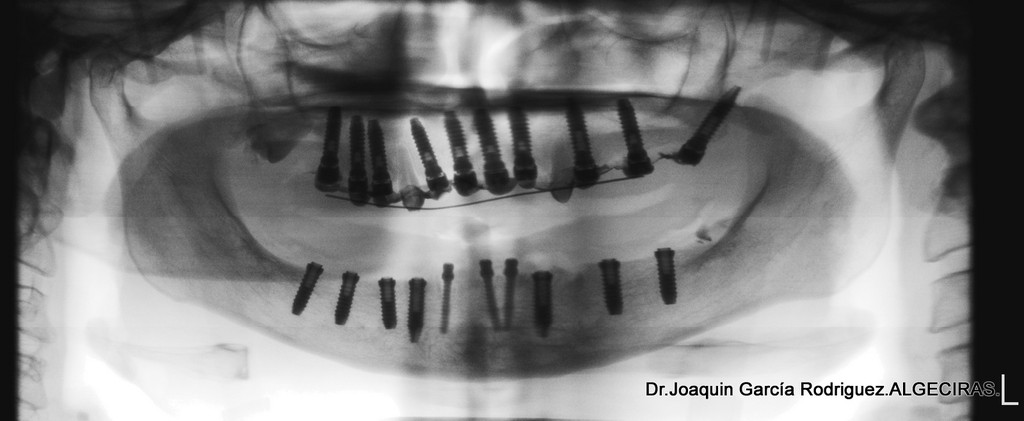

• La prótesis hibrida es una extructura de metal que se soporta entre 6 a 8 implantes al que se le añade unas tabillas de dientes prefabricados que pueden ser de acrílico o de cerámica.

• La prótesis ceramometálica se sustenta entre 8 y 10 implantes para repartir cargas de 14 dientes en cada maxilar. A diferencia de la anterior, aquí los dientes se diseñan a mano, capa a capa por el ceramista.

En este caso clínico mostramos la diferencia entre una Prótesis Hibrida o Mesoextructura y una Rehabilitación ceramometálica.